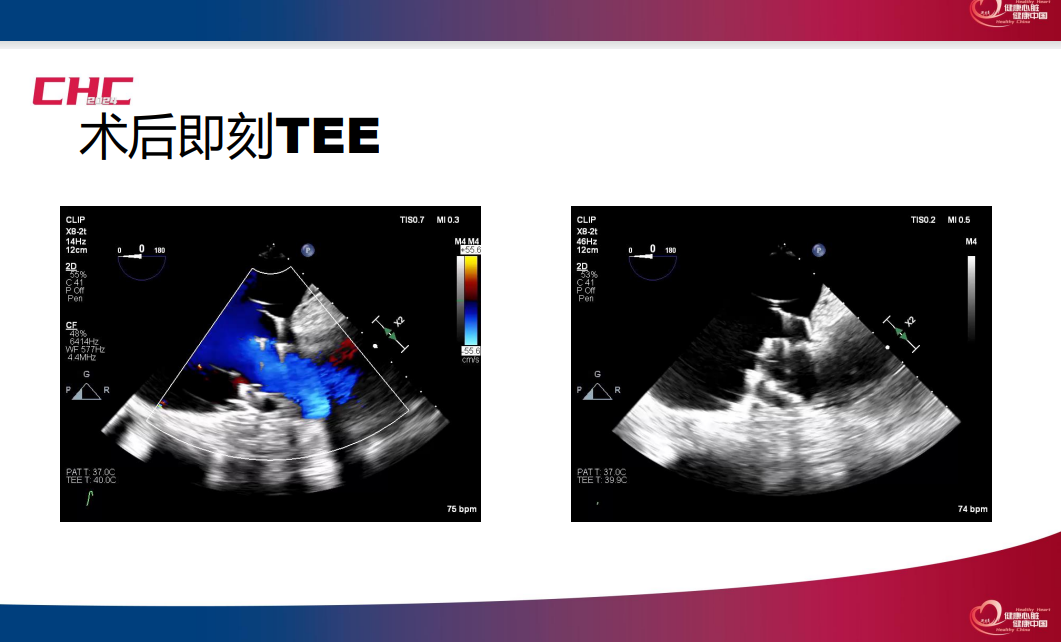

施浩教授介绍了一例成功进行单纯超声引导下经导管三尖瓣置换术的病例,从术前CT评估,术前3D打印体外模拟多方面详细介绍了术前评估流程,并且展示了术中超声过程。

赵广智教授以两例成功进行全超声引导下三尖瓣TEER的病例为例,详细介绍了该技术的术中操作步骤,提供了超声引导三尖瓣TEER的技巧和建议,包括探头操作和多级成像。